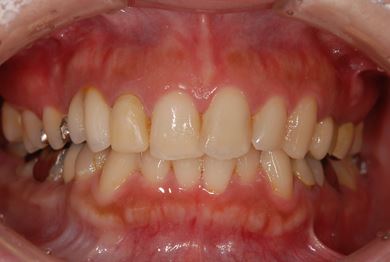

インプラントの症例写真 IMPLANT

抜歯即日スピードインプラント治療

| 性別/年齢 | 女性 / 29歳 | ||||||||||||||||||||||||||||||||

| 主訴 | 以前治療中のままだった部位の歯の根に膿が溜まって、痛みと腫れが出た。応急処置で切開して膿は取ってもらったが、根の治療がまだなので、お願いしたい。 | ||||||||||||||||||||||||||||||||

| 治療方針 | 抜歯と同時にインプラント埋入を行い、治療期間を短縮する。 | ||||||||||||||||||||||||||||||||

| 治療内容 | インプラント2本(抜歯即日スピードインプラント)、ハイブリッドセラミッククラウン3本 | ||||||||||||||||||||||||||||||||